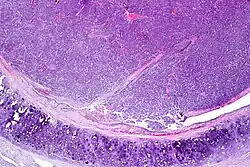

Atypical pulmonary carcinoid. H&E stain.

Atypical carcinoid tumors have increased mitotic activity (2-10 per 10 HPF), nuclear pleomorphism or foci of necrosis.

Atypical carcinoid of the lung exhibiting endobronchial growth, increased mitotic activity was seen (2-10 per 10 HPF). H&E stain.